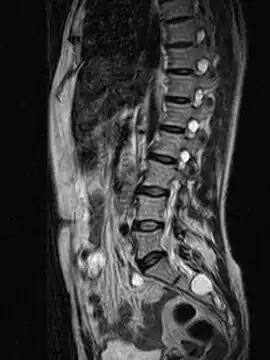

MRI image showing a Tarlov cyst

MRI sagittal image of sacral and dorso-lumbar perineural cysts.

MRI

MRI, or Magnetic Resonance Imaging, is considered the imaging study of choice in identifying Tarlov cysts. MRI provides better resolution of tissue density, absence of bone interference, multiplanar capabilities, and is noninvasive. Plain films may show bony erosion of the spinal canal or of the sacral foramina. On MRI pictures, the signal is the same as the CSF one.